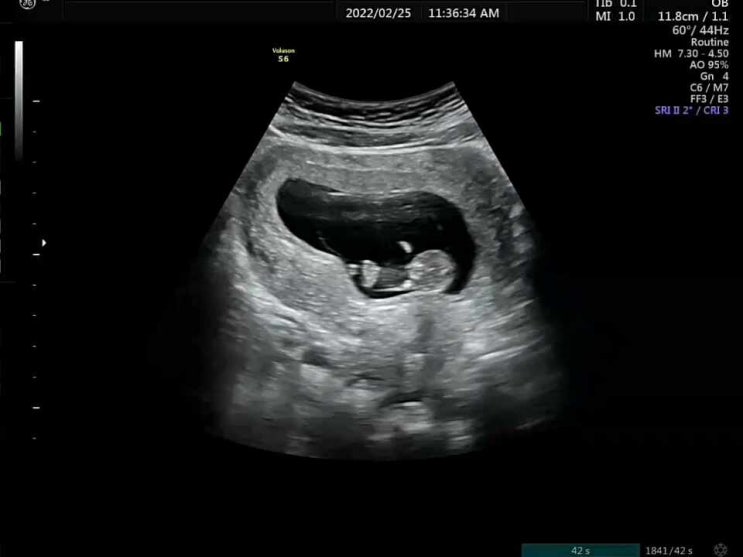

[임신27주1일&28주4일]

지난 정밀초음파때 팔꿈치로 심장혈관을 가리는바람에 2차정밀초음파검진을 보러갔다? 결과는 모두모두 ...